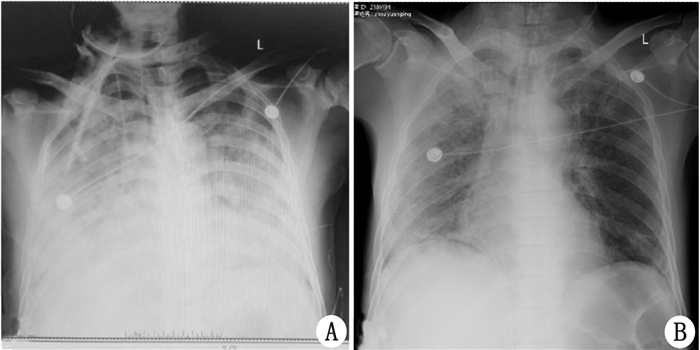

1 资料与方法病例1患者,男,40岁,既往体健,事发前身高175 cm,因“接触高压粗酚后昏迷6 h”于2016年10月9日18:00入院。入院前6 h在工作过程中, 因误操作致高压粗酚泄漏,喷射至患者双手、双上肢前臂、下颌部、双下肢小腿处,约3 min后出现意识障碍,表现为昏迷、呼之不应,约30 min内急至当地医院予生理盐水清洁皮肤、导尿处理,导出棕褐色尿液少许约100 mL,为进一步诊治转本院,转运途中意识渐好转。入院体温35.6℃, 心率62次/min, 呼吸12次/min, 血压146/103 mmHg(1 mmHg=0.133 kPa);神志嗜睡, 双侧瞳孔等大等圆,直径3 mm对光反射灵敏;受累及部位皮肤呈黑褐色(图 1 A、B、C),约占皮表面积25%,皮温高于临界皮肤;心肺腹、神经反射未见异常,尿呈棕褐色(图 1 A);初步诊断为:① 粗酚中毒; ② 多器官功能障碍综合征(MODS)?入院后化验示:K+ 5.2 mmol/L; 肌酐167.0 μmol/L, 尿素氮8.9 mmol/L, 结合胆红素8.5 μmol/L, 非结合胆红素33.5 μmol/L,肌红蛋白161.7 ng/mL,肌钙蛋白0.015 ng/mL, 心电图示T波高尖;彩超示多浆膜腔积液;立即给予0.45%医用酒精反复冲洗、擦拭,清除体表粗酚,并给予血液灌流,拉氧头孢、左奥硝唑、利奈唑胺等抗感染,保护各器官功能等支持对症治疗;但入院后6 h尿量减至56 mL,肌红蛋白、肌酐、尿素氮持续升高,考虑急性肾衰竭,遂于入院后12 h起行血液透析治疗,次日患者逐渐出现呼吸困难、低氧血症、肺部浸润阴影(图 2 A)、肝功能损害、心功能急剧下降(BNP20 365 pg/mL),呼吸支持由面罩吸氧逐步升级为无创呼吸机、气管插管有创呼吸机辅助呼吸,患者呼吸窘迫仍呈加重趋势、低氧血症难以纠正,容量控制通气[(6 mL/kg理想体质量,FiO2 100%,PEEP 12 cmH2O(1 cmH2O=0.098 kPa),呼吸频率18次/min)]下,动脉血气分析示PaO2为52.5 mmHg,考虑急性呼吸窘迫综合征(ARDS)、MODS诊断成立,为替代心肺功能、改善氧合指数、为受损肺提供修复时间,与家属沟通后于入院后5 d给予VV-ECMO应用,氧分压明显升高,心衰、肾衰竭、感染指标等明显改善;继续应用ECMO、呼吸机、连续肾脏替代治疗(CRRT)、抗感染及输血、血管活性药物、雾化排痰、抗凝、营养心肌等对症支持治疗,同时辅以化学烧伤的规范换药等局部皮肤处理(图 1 D、E),血液净化20 d后尿量逐渐恢复至3 000 mL/d左右停用CRRT,ECMO应用12 d后病情基本稳定,胸片示肺部透亮度增加(图 2 B)给予脱离ECMO,8 d后逐步撤离呼吸机,转入普通病房继续康复治疗约20 d后好转出院,随访截止目前近1年,未诉不适。

| A提示ECMO治疗前双肺弥漫浸润阴影;B为病情好转后ECMO撤机前,肺部浸润病灶较前明显吸收, 右肺肺纹理稍增粗 图 2 患者肺片变化 |